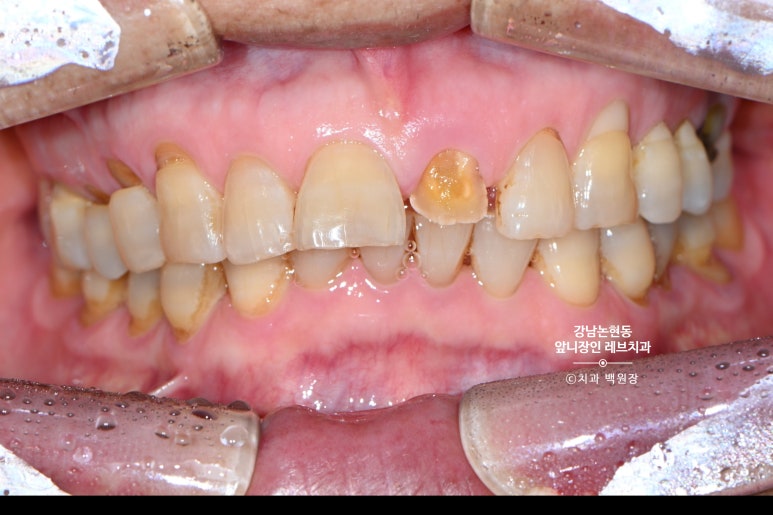

60대 남자 환자분이 저희 치과에 내원하셨습니다.

앞니가 부러져서 오신거에요.... 생니가 그냥 부러져 버렸습니다.

아마 씹는 힘도 세시고, 물리는 형태도 깊게 물리는 형태셔서 앞니가 너무 큰 힘을 받았을겁니다.

누적된 외력에 어느날 치아가 부러져 버린거죠.

윗니 아랫니 공간을 보시면, 치아가 얼마나 부러질만한 힘을 받았을지 상상해볼 수 있습니다..

고생했을 앞니.. 환자분은 다른 치과에서 뽑고 임플란트 해야한다는 설명을 듣고 살릴 수 없는지 문의해보러 오셨습니다.